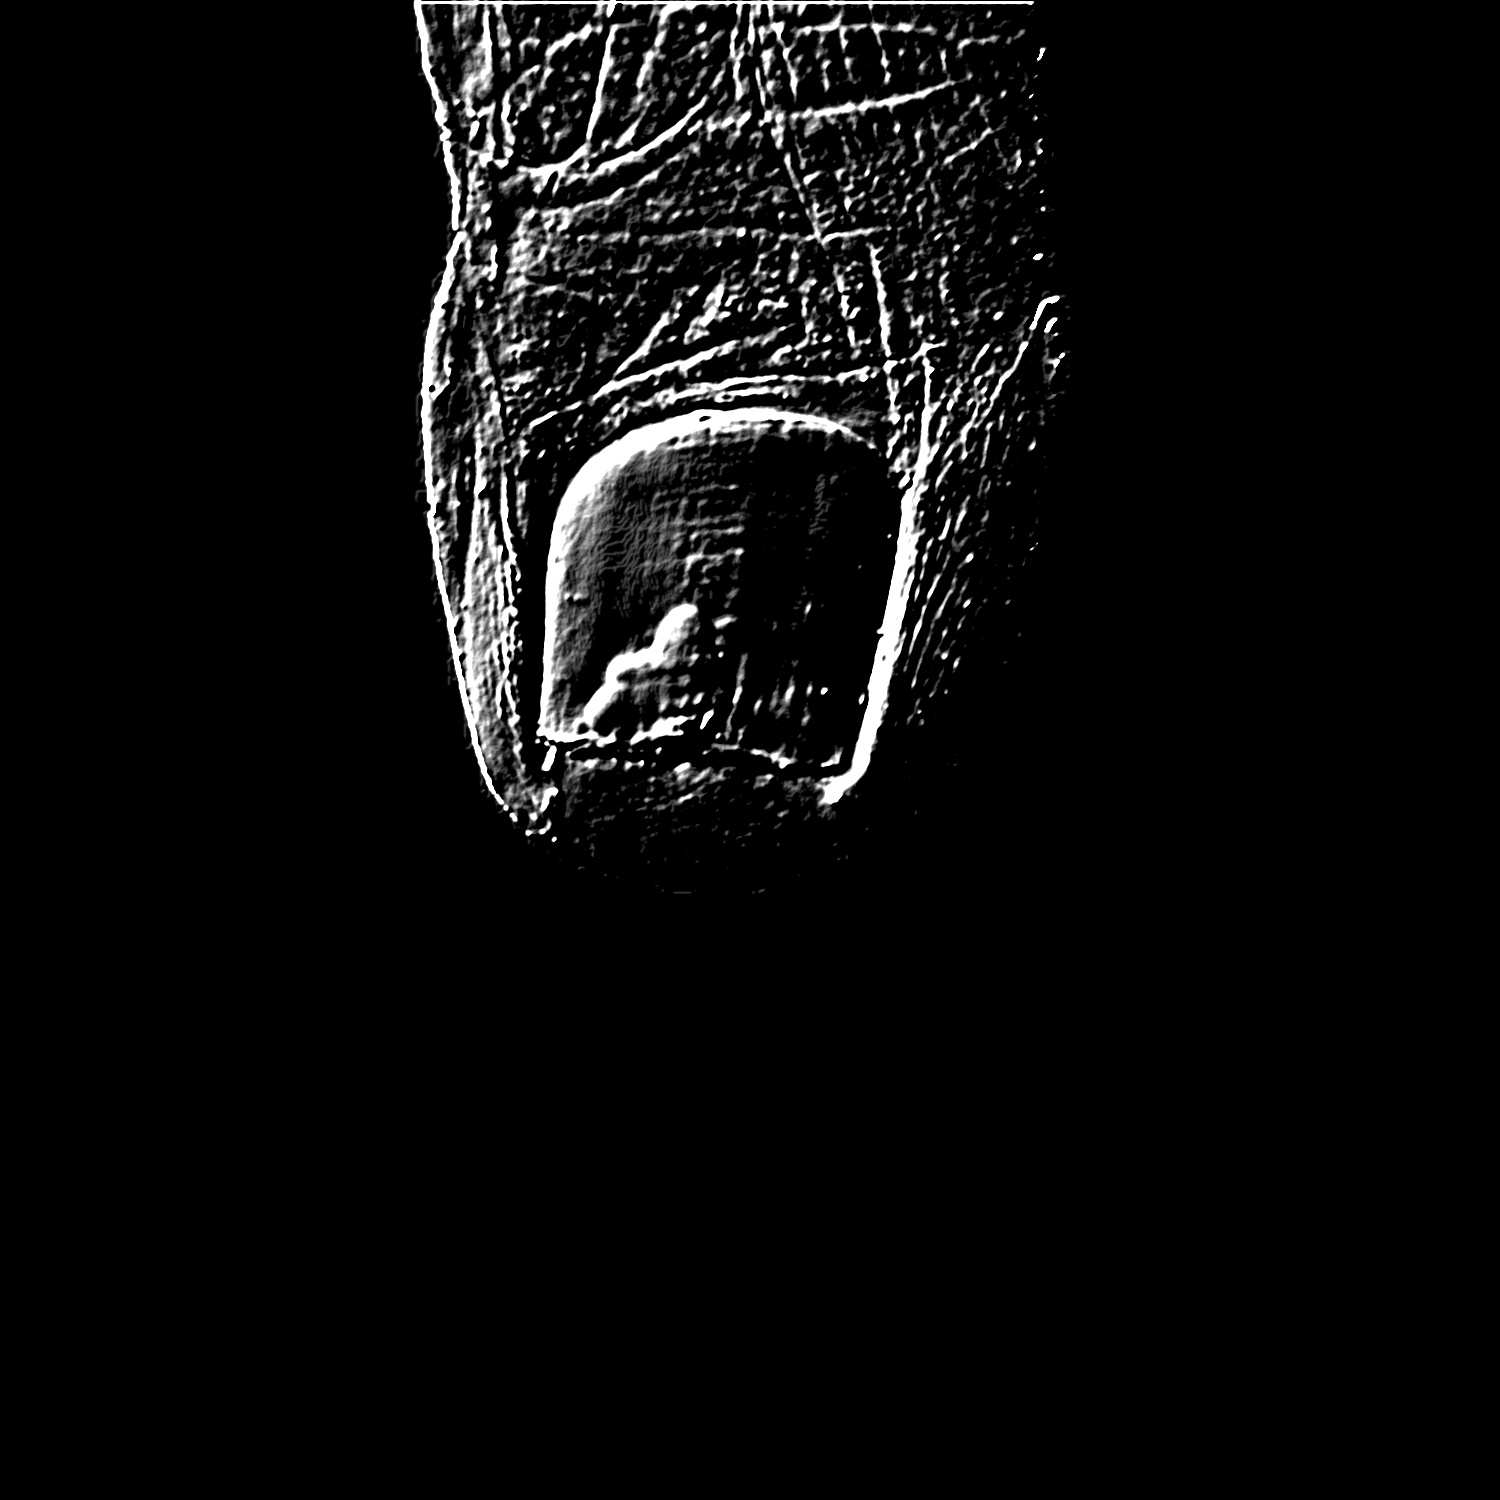

By adding up each one of the Canny edge instances we obtain a cumulative contour image, shown in Fig. 5(a).

Onto that edge image, we apply the Hough transform to locate the tip of the toe. Due to its position and size, the area inside this pattern contains the nail. So, we apply the circular Hough transform on the edge image and we select the best candidate as the nearest circle to the template bottom right corner that has a predefined percentage of its area within the foot ROI (specifically, we choose a threshold of ). Also, the computed circles are limited to radius between 0.85 cm and 1.75 cm. The selected circle is shown in Fig. 5(b). We remark that this circular pattern captures the tip of the toe but does not locate the nail with acceptable accuracy.

Finally, we detect the circle that better fits the nail using a second Hough transform. We discard the edges far from the tip of the toe circle (see Fig. 5(c)), so that we mainly keep the nail edges. Thus, this second Hough transform is prone to detect the circle that best fits the nail. Also, we constrain the radius of this circle according to the size of the tip of the toe. Specifically, we expect the nail radius to be smaller than the radius of the tip of the toe circle (see Fig. 5(b)) but bigger than half of its measure. The most prominent circle (see Fig. 5(d)) is the one selected as nail circle. Experimentally, the results of this process have proved to always find a location on the nail (the circle center) and a good estimation of the nail size (derived from the radius).